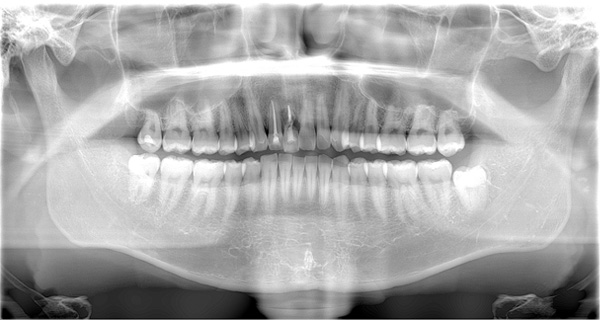

AFTER

| 年代・性別 | 50代 男性 |

|---|---|

| 主訴 | 右上下の歯が痛い |

| 治療期間 | 約12ヶ月 |

| 費用 | 2,500,000円 |

| 治療内容 | インプラント、骨造成、結合組織移植、セラミック修復 |

| 治療に伴うリスク | インプラント周囲炎 セラミックの破折、脱離 |

*キャンセルポリシーをご一読のうえご予約ください